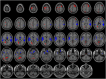

Methods: Patients with biologically-confirmed COVID-19 and neurological manifestations undergoing a brain MRI with technically adequate arterial spin labeling (ASL) perfusion were included in this retrospective multicenter study. ASL maps were jointly reviewed by two readers blinded to clinical data. They assessed abnormal perfusion in four regions of interest in each brain hemisphere: frontal lobe, parietal lobe, posterior temporal lobe, and temporal pole extended to the amygdalo-hippocampal complex.

Results: Fifty-nine patients (44 men (75%), mean age 61.2 years) were included. Most patients had a severe COVID-19, 57 (97%) needed oxygen therapy and 43 (73%) were hospitalized in intensive care unit at the time of MRI. Morphological brain MRI was abnormal in 44 (75%) patients. ASL perfusion was abnormal in 53 (90%) patients, and particularly in all patients with normal morphological MRI. Hypoperfusion occurred in 48 (81%) patients, mostly in temporal poles (52 (44%)) and frontal lobes (40 (34%)). Hyperperfusion occurred in 9 (15%) patients and was closely associated with post-contrast FLAIR leptomeningeal enhancement (100% [66.4%-100%] of hyperperfusion with enhancement versus 28.6% [16.6%-43.2%] without, p = 0.002). Studied clinical parameters (especially sedation) and other morphological MRI anomalies had no significant impact on perfusion anomalies.

Conclusion: Brain ASL perfusion showed hypoperfusion in more than 80% of patients with severe COVID-19, with or without visible lesion on conventional MRI abnormalities.